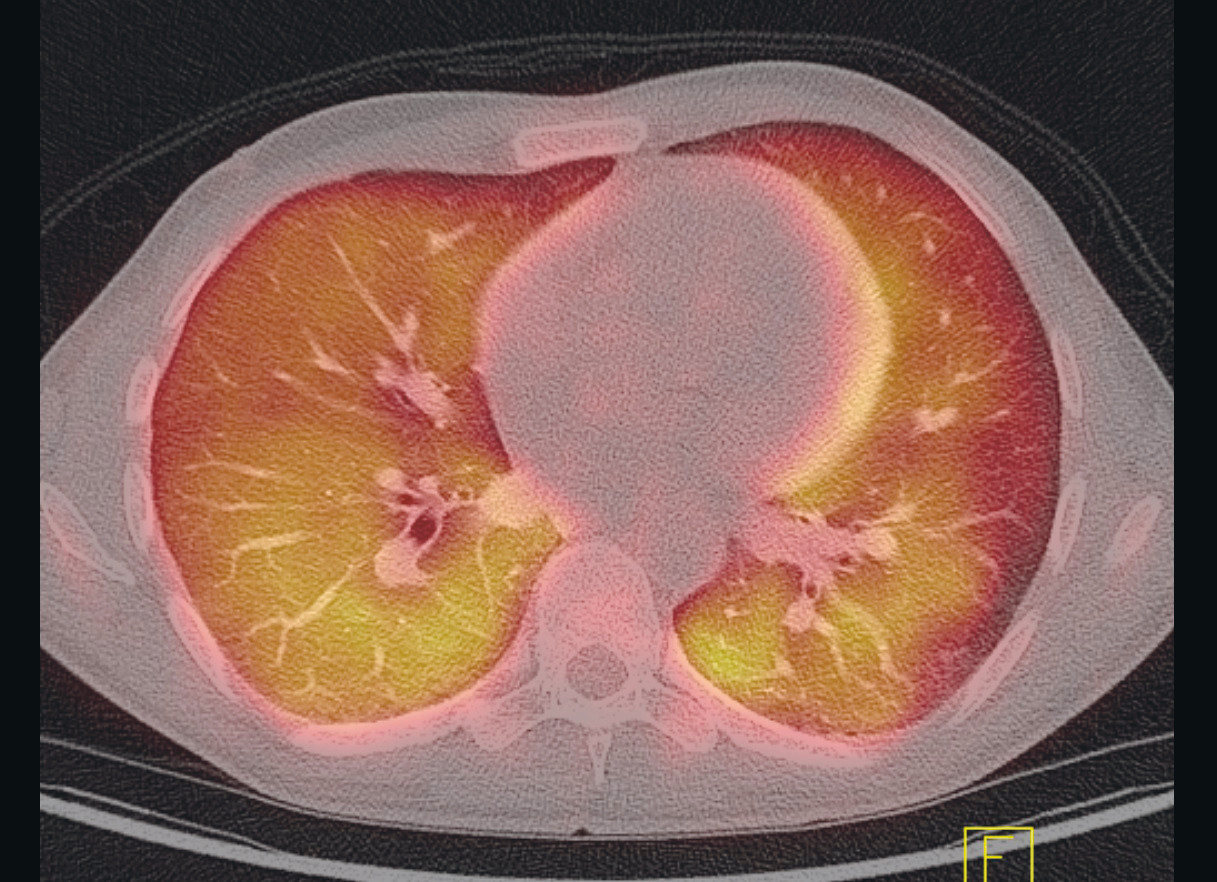

De neste dagene hadde pasienten fortsatt episoder med subfebrilia og økende dyspné, i tillegg til generelt nedsatt allmenntilstand. Det ble utført PET-CT, som viste tegn til utbredt, diffust opptak av ¹⁸F-fluordeoksyglukose (¹⁸F-FDG) i begge lunger samt reaktiv milt og beinmarg (figur 1). Differensialdiagnoser som ble foreslått, inkluderte infeksjon, lymfom og hypersensitivitetspneumonitt.

PET-CT er en modalitet der PET og multisnitt-CT kombineres. Den vanligste markøren er radioaktivt ¹⁸F-FDG, en glukoseanalog som fungerer som markør for metabolsk aktivitet i vev. PET-detektoren registrerer hvor den radioaktive strålingen konsentreres i kroppen, og dette korreleres til de anatomiske strukturene på CT-bildene. Økt ¹⁸F-FDG-opptak på PET-CT kan f.eks. ses ved økt celledeling i maligne svulster, økt aktivitet i leukocytter ved infeksjoner og ved ikke-infeksiøse inflammasjonstilstander.